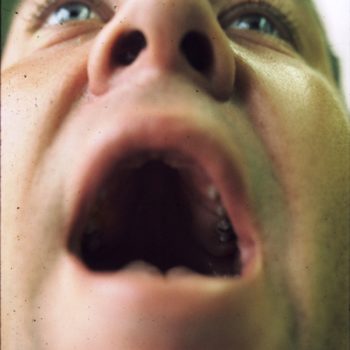

Scalp Hair

Note what signs you see.

I (N. Zymak-Zakutnia, M.D.) see:

- Scalp hair, coarse.

- Scalp hair, double whorl, right clockwise and left anti-clockwise.

- Premature canocity.

PERSPECTIVE: Dramatic example of disrupted hair patterning likely to be related to concurrent microcephaly. Also an illustration of deformation of a “comb-like” hair standing on ends mostly seen in non-human mammals – dermatoglyphic patterns provide equally dramatic illustrations in particular on fingertip with whirls patterns.